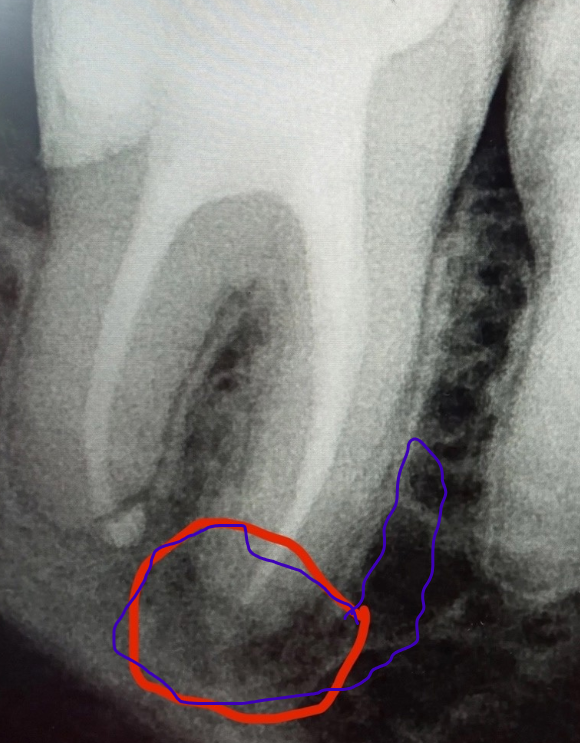

Pawa213123 Опубликовано 25 февраля, 2025 Поделиться Опубликовано 25 февраля, 2025 Зуб без нерва. Пол года назад делали снимок обычный + КТ. КТ показал, что в зубе нет инфекции. А на новом снимке вдруг что-то стало видно. Это артефакт какой-то или что? Я выделил это черным цветом. Ссылка на комментарий

Женька Опубликовано 25 февраля, 2025 Поделиться Опубликовано 25 февраля, 2025 @Pawa213123 Здравствуйте. Снимки под разными углами, на последнем ещё один канал просняли просто. 1 час назад, Pawa213123 сказал: Может тогда уж лучше удалить этот зуб, да протез поставить? Не лучше. Ставьте коронку, если родные зубы Вам дОроги. 1 час назад, Pawa213123 сказал: Раскол зуба это же не больно? Ещё как больно. Любое жевание и смыкание зубов будет давать чувствительность. Поэтому, не мудрите. Ваш доктор Вам верно сказал, поставьте коронку. 1 Ссылка на комментарий

Pawa213123 Опубликовано 25 февраля, 2025 Автор Поделиться Опубликовано 25 февраля, 2025 И вот это воспаление тоже пойдет не в кость, а либо по пути, который я снова изобразил фиолетовым, либо же в бока, чтобы образовать свищ, правильно? Ссылка на комментарий